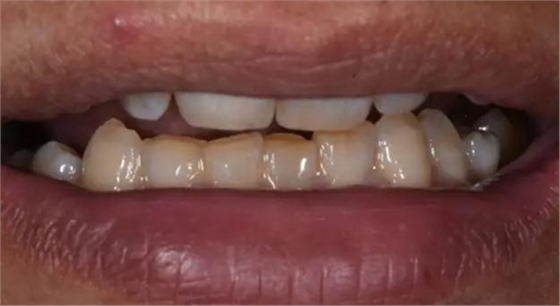

術后口內照片

修復體戴入口內后照片,與鄰牙鄰接良好。